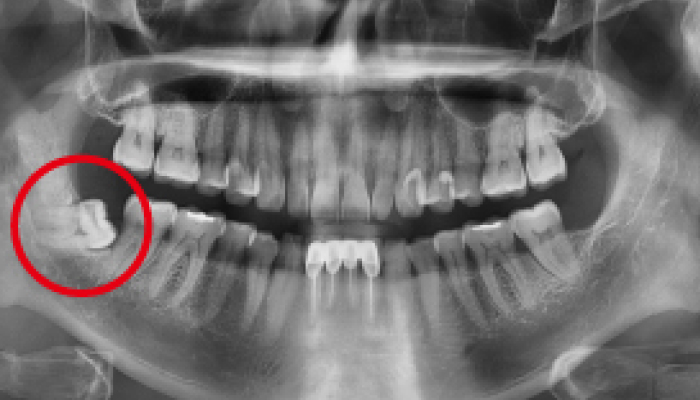

• 치료전

치료후